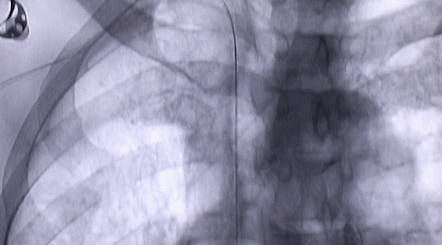

1月12日,西安國(guó)際醫(yī)學(xué)中心醫(yī)院心臟外科郭穎強(qiáng)主任團(tuán)隊(duì)成功為一名腹主動(dòng)脈閉塞、右側(cè)腎動(dòng)脈閉塞、左側(cè)腎動(dòng)脈重度狹窄、腹壁淺表動(dòng)脈側(cè)支循環(huán)形成、高血壓病3級(jí)(極高危組)合并閉塞性周圍動(dòng)脈粥樣硬化、急性腎功能不全的老年患者實(shí)施腎動(dòng)脈球囊擴(kuò)張 腎動(dòng)脈支架植入術(shù) 動(dòng)脈血栓抽吸術(shù) 髂動(dòng)脈開通術(shù),治好了困擾患者多年的頑固性高血壓。患者目前康復(fù)良好,將于近日出院。

按照術(shù)前制定的方案,郭穎強(qiáng)主任和楊金保博士首先嘗試開通閉塞的右腎動(dòng)脈,但由于血栓機(jī)化、鈣化嚴(yán)重,右腎動(dòng)脈難以開通。遂謹(jǐn)慎擴(kuò)張狹窄的左腎動(dòng)脈,并成功植入一枚支架。之后經(jīng)過(guò)反復(fù)旋磨、抽吸,順利開通髂動(dòng)脈,但腹主動(dòng)脈閉塞段仍難以擴(kuò)通。此時(shí),患者居高不下的血壓很快恢復(fù)到正常水平。